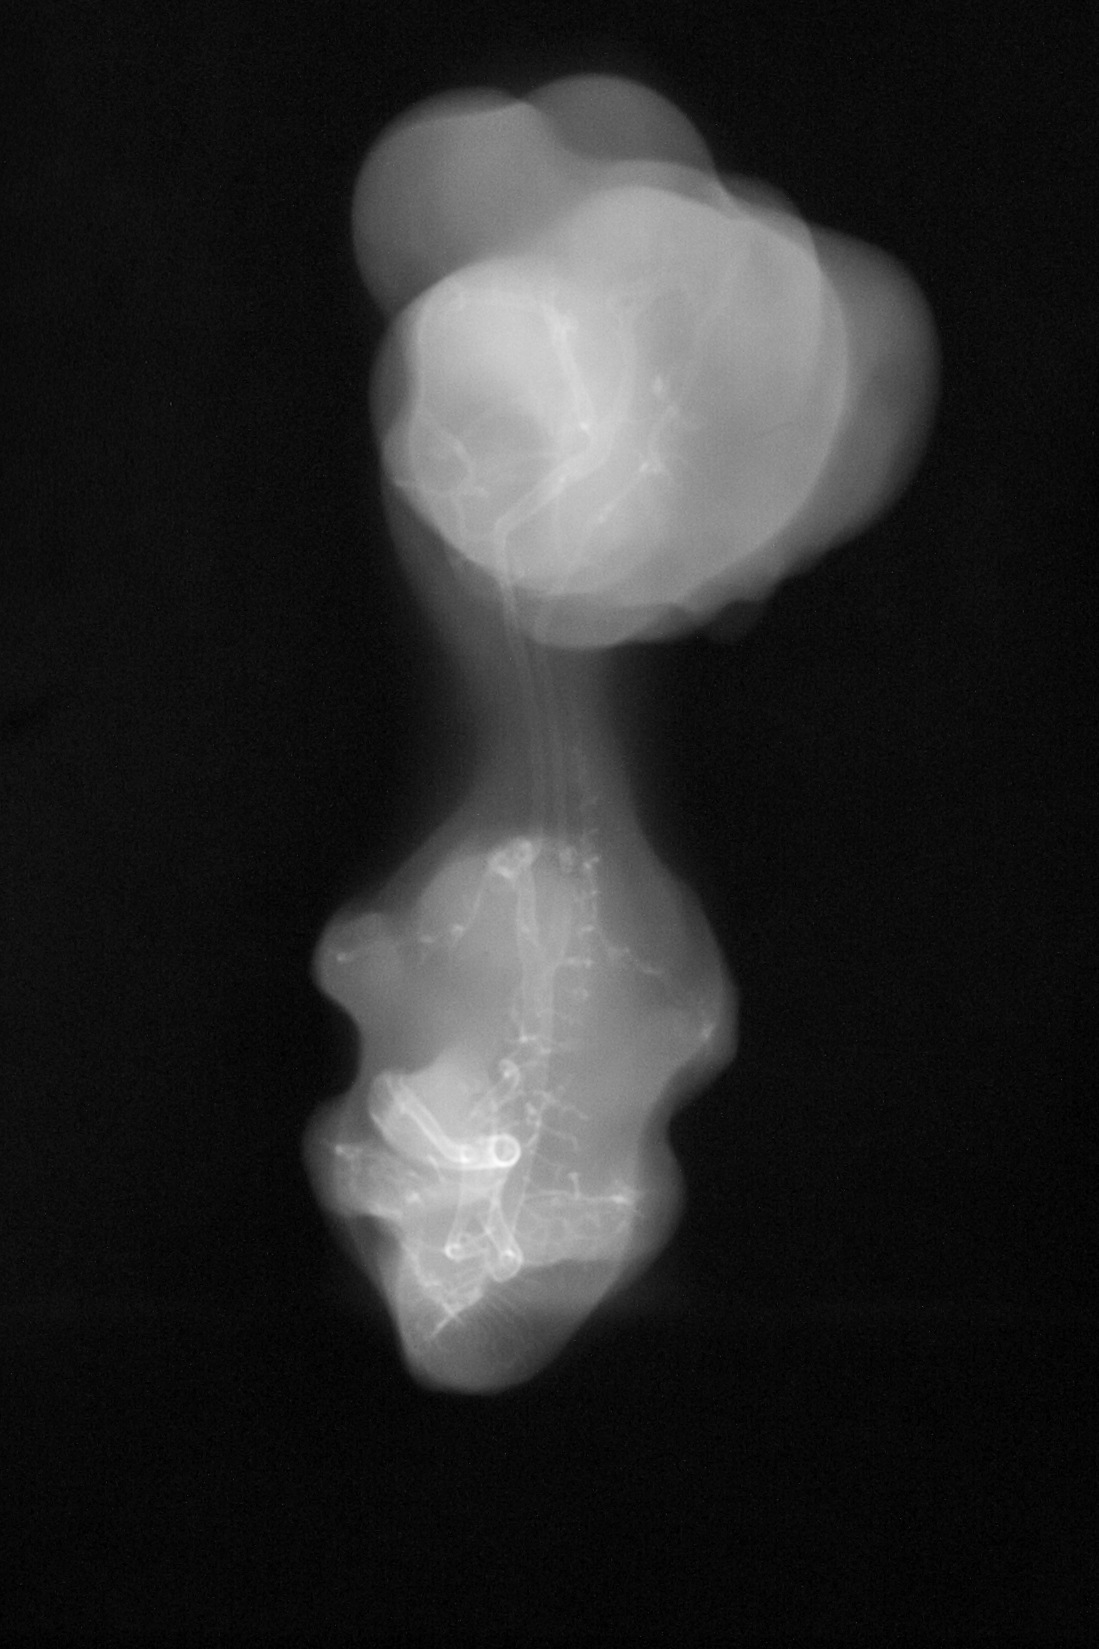

Chick Embryo Microangiography

Hamburger-Hamilton (HH) Stage 30 (approx. 6.5 days)

Drawing